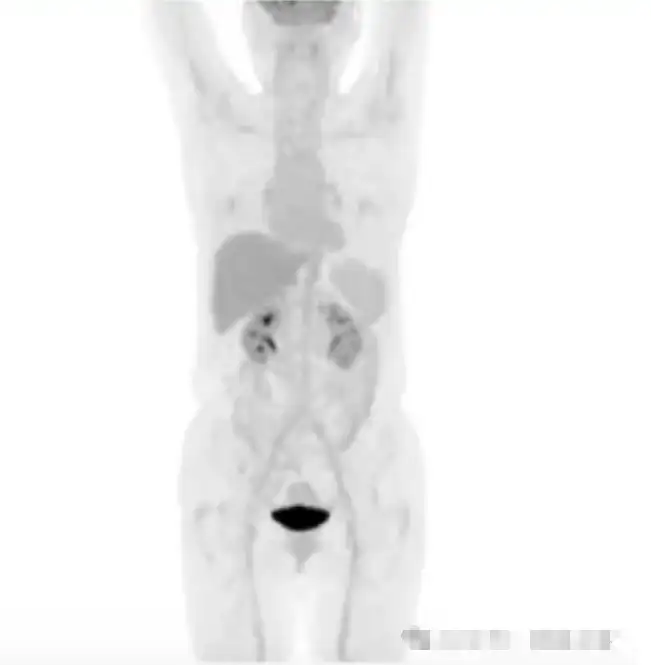

患者在检查当日早上自己测过血糖,血糖值为12.3mmol/l,随后自己使用了短效胰岛素,在进行PET/CT检查前患者向医生说明了自己的用药情况,医生建议取消当日的PET/CT检查,在反复沟通过后,患者仍坚持当日检查。PET/CT显像后,全身肌肉呈对称性明显显影,肝血池SUVmax 1.4,右肺下叶病灶SUVmax 0.9,图像质量不能满足诊断要求。

医生建议2日后重新进行检查,并且检查当日要停用胰岛素,左图为患者使用胰岛素后进行PET/CT显像检查的图像,全身肌肉对称性显影;右图为患者停用胰岛素后的显像图像。